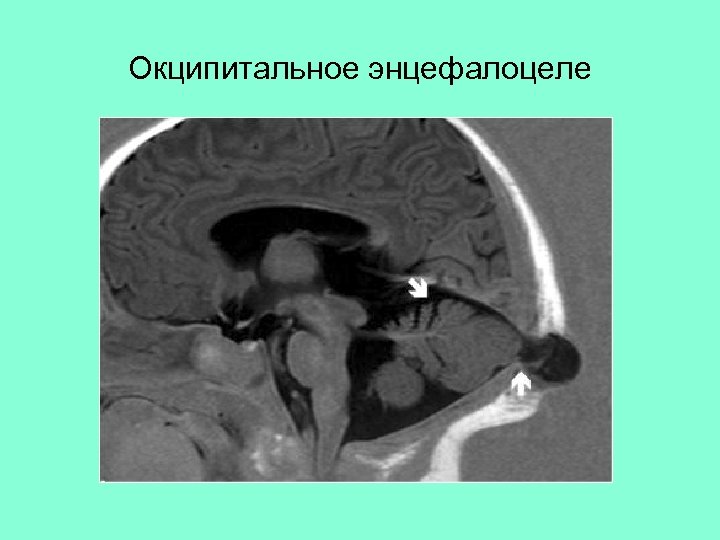

Окципитальное энцефалоцеле